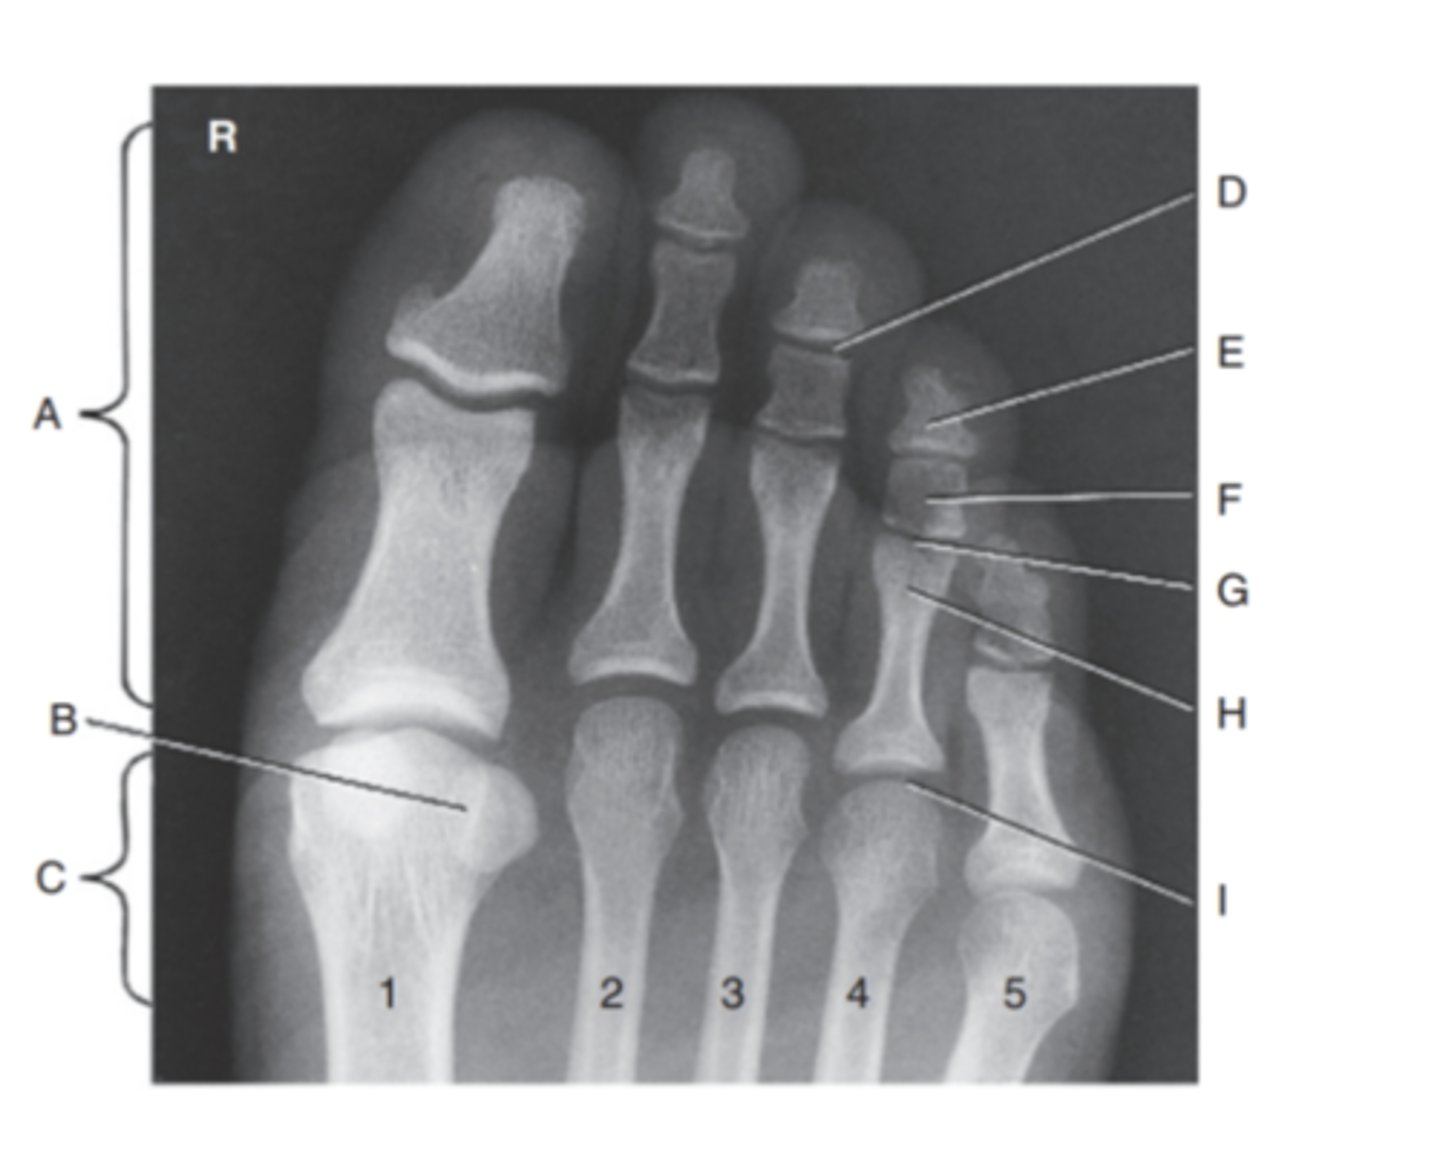

(PA TOES) what is A?

phalanges

what is B?

sesamoids

what is C?

metatarsals

what is D?

Distal interphalangeal joint

what is E?

distal phalanx

what is F?

middle phalanx

what is G?

Proximal interphalangeal joint

what is H?

proximal phalanx

what is I?

Metatarsophalangeal joint